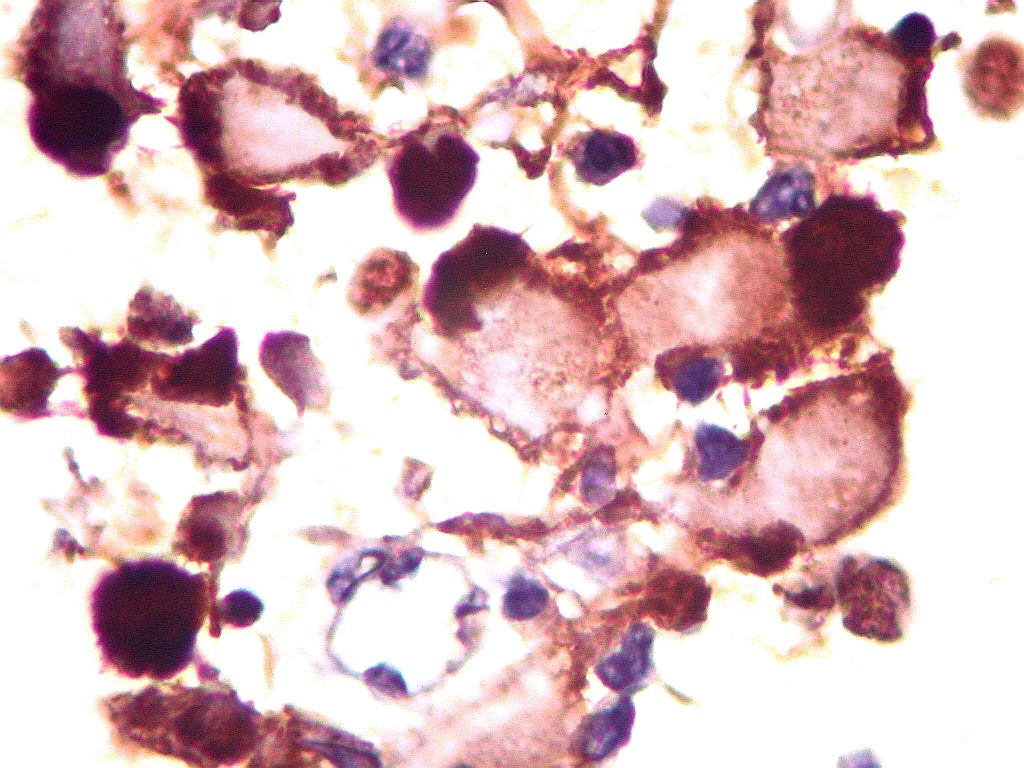

MAP2.   Microtubular associated protein,  marcador de diferenciação  neuronal. Universalmente positivo nas células deste ATRT.  Folículo linfóide  negativo (controle  interno).  Marcação é citoplasmática, na periferia do citoplasma.  Corpúsculo rabdóide negativo.  Para mais sobre MAP2, clique.